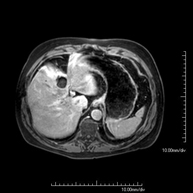

Prova diagnòstica no invasiva que consisteix en l'obtenció d'imatges d'alta definició anatòmica de la pelvis masculina mitjançant l'ús d'un camp electromagnètic i ones de ràdio (amb un emissor i un receptor). No utilitza radiació ionitzant. No requereix preparació prèvia. En algunes ocasions necessita l'ús de contrast paramagnètic (Gadolini) per caracteritzar les lesions. Aquesta prova permet valorar òrgans com la bufeta urinària, la unió entre els urèters i la bufeta, la pròstata, les vesícules seminals, la uretra i els ossos de la pelvis, entre d'altres. - RM de Fetge

Prova diagnòstica no invasiva que consisteix en l'obtenció d'imatges d'alta definició anatòmica del fetge mitjançant l'ús d'un camp electromagnètic i ones de ràdio (amb un emissor i un receptor). No utilitza radiació ionitzant. Es realitza per estudiar qualsevol lesió localitzada en el fetge. Normalment es requereix l'ús de contrast paramagnètic (Gadolini) per caracteritzar les lesions. És necessari realitzat la prova en dejú (6 hores). - RM de Ronyons